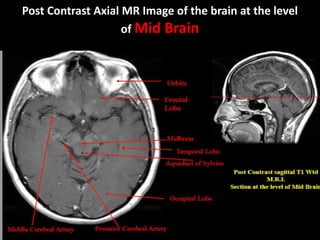

Post Contrast Axial MR Image of the brain at the level

of Mid Brain